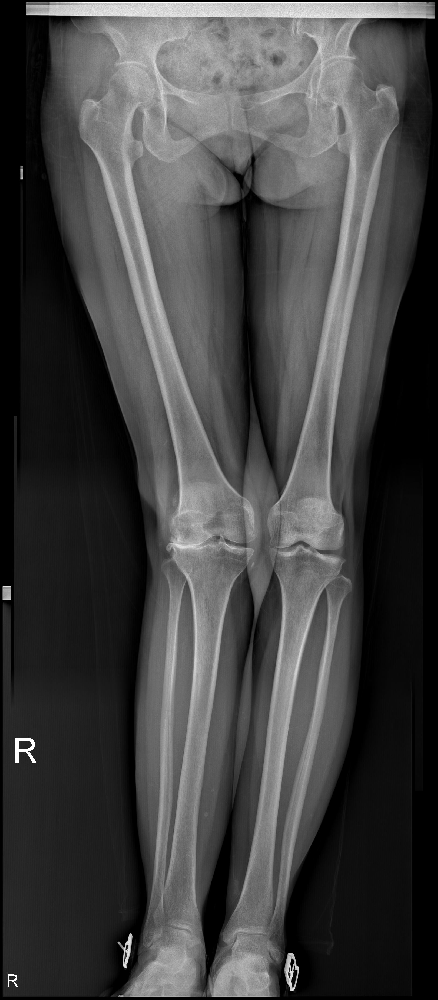

10年前,賈知梅的右膝關(guān)節(jié)開(kāi)始疼痛,并伴隨著獨(dú)特的外翻畸形。這種痛苦持續(xù)了10年,時(shí)斷時(shí)續(xù),隨著勞累的增加而加劇。只有休息,她才能稍稍得到緩解;負(fù)重時(shí),疼痛則變得更加明顯。為了緩解這種癥狀,賈知梅曾前往當(dāng)?shù)氐脑\所接受了針灸、按摩理療,效果也令她稍為舒服一些。

然而,一年前,賈知梅的右膝關(guān)節(jié)疼痛再度加重,甚至使她失去了行走的能力。在疼痛急劇惡化時(shí),她只能依靠口服止痛藥稍稍緩解一些痛楚。面對(duì)這樣的困境,賈知梅選擇了市中區(qū)誠(chéng)德骨科醫(yī)院入院,并接受了一項(xiàng)名為右膝外側(cè)固定平臺(tái)單髁置換術(shù)的手術(shù)。